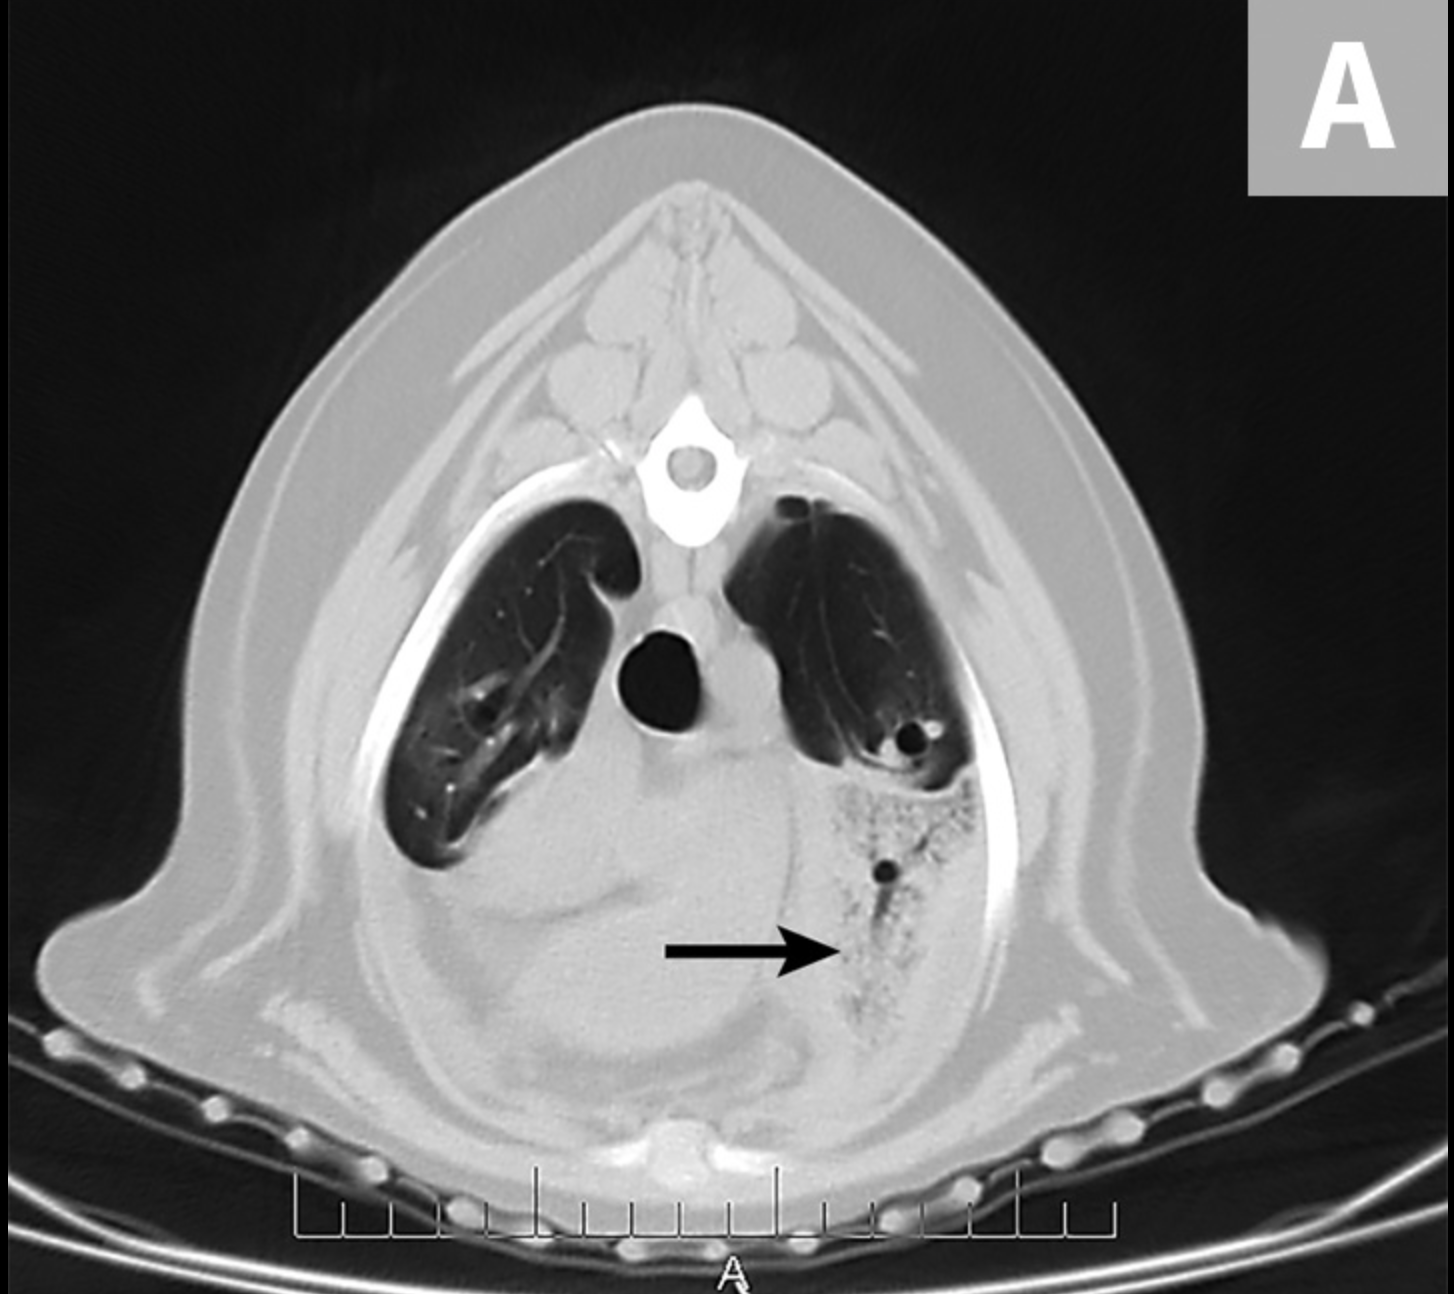

La TC mostró derrame pleural moderado bilateral con una apariencia anormal del lóbulo craneal izquierdo del pulmón, colecciones de gases punteados y truncamiento del bronquio que sugirió LLT (Figura 4).